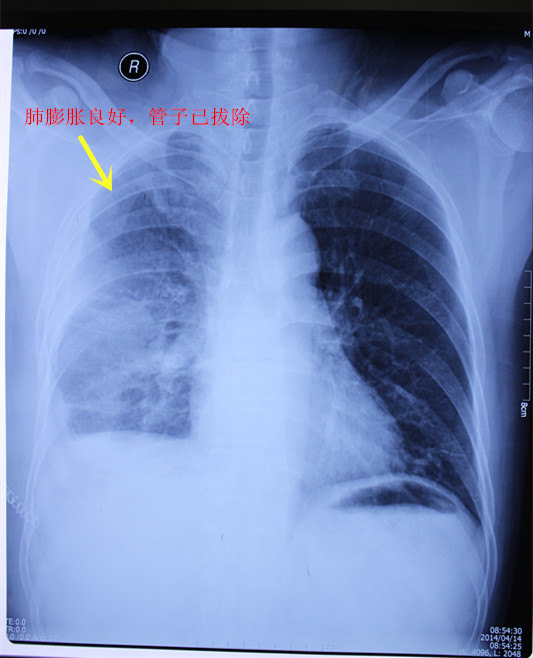

时间慢慢流逝,我努力配合治疗,坚持不懈。终于,在经过一段时间的治疗后,医生告诉我,我的肺部的空洞已经开始闭合了。那一刻,我欣慰而感动,这是我坚持治疗的动力和信心所在。